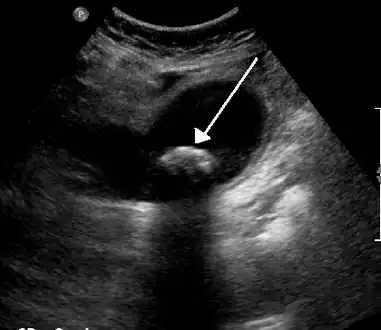

| Biliary colic is often related to a stone in the gallbladder | |

Diagnosis is guided by the person's presenting symptoms and laboratory findings. The gold standard imaging modality for the presence of gallstones is ultrasound of the right upper quadrant. There are many reasons for this choice, including no exposure to radiation, low cost, and availability in city, urban, and rural hospitals. Gallstones are detected with a specificity and sensitivity of greater than 95% with ultrasound.[18] Further signs on ultrasound may suggest cholecystitis or choledocholithiasis.[12] Computed Tomography (CT) is not indicated when investigating for gallbladder disease as 60% of stones are not radiopaque.[12] CT should only be utilized if other intra-abdominal pathology exists or the diagnosis is uncertain.[19] Endoscopic retrograde cholangiopancreatography (ERCP) should be used only if lab tests suggest the existence of a gallstone in the bile duct.[12] ERCP is then both diagnostic and therapeutic.